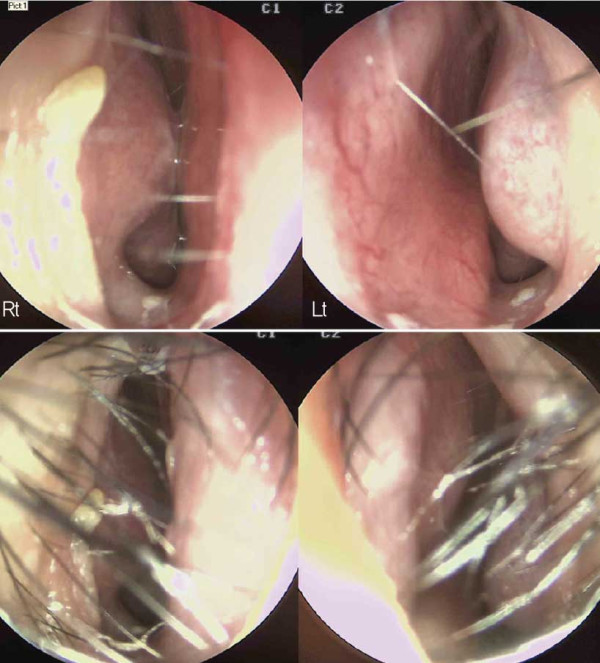

![]()

수술 전 내시경 사진. 비중격 상단부가 좌측으로 만곡되어 있으며, 미단부는

우측으로 전위된 모습이 관찰되었다. 비중격 미단부 변형 및 비익의 변형으로

인한 우측 비밸브 협착도 확인되었다

내시경 검사상 비중격 상단부가 좌측으로 만곡되고 미단 부가 우측으로 전위되어 있었다. 비중격 미단부와 비익의 선천적 변형으로 인한 우측 비밸브 협착도 관찰되어, 비중 격 및 비밸브 교정술과 하비갑개점막절제술을 계획하였다. 해당 환자는 외형적인 비대칭뿐만 아니라 기능적인 불 편함으로 인해 일상생활에서 어려움을 겪었다.